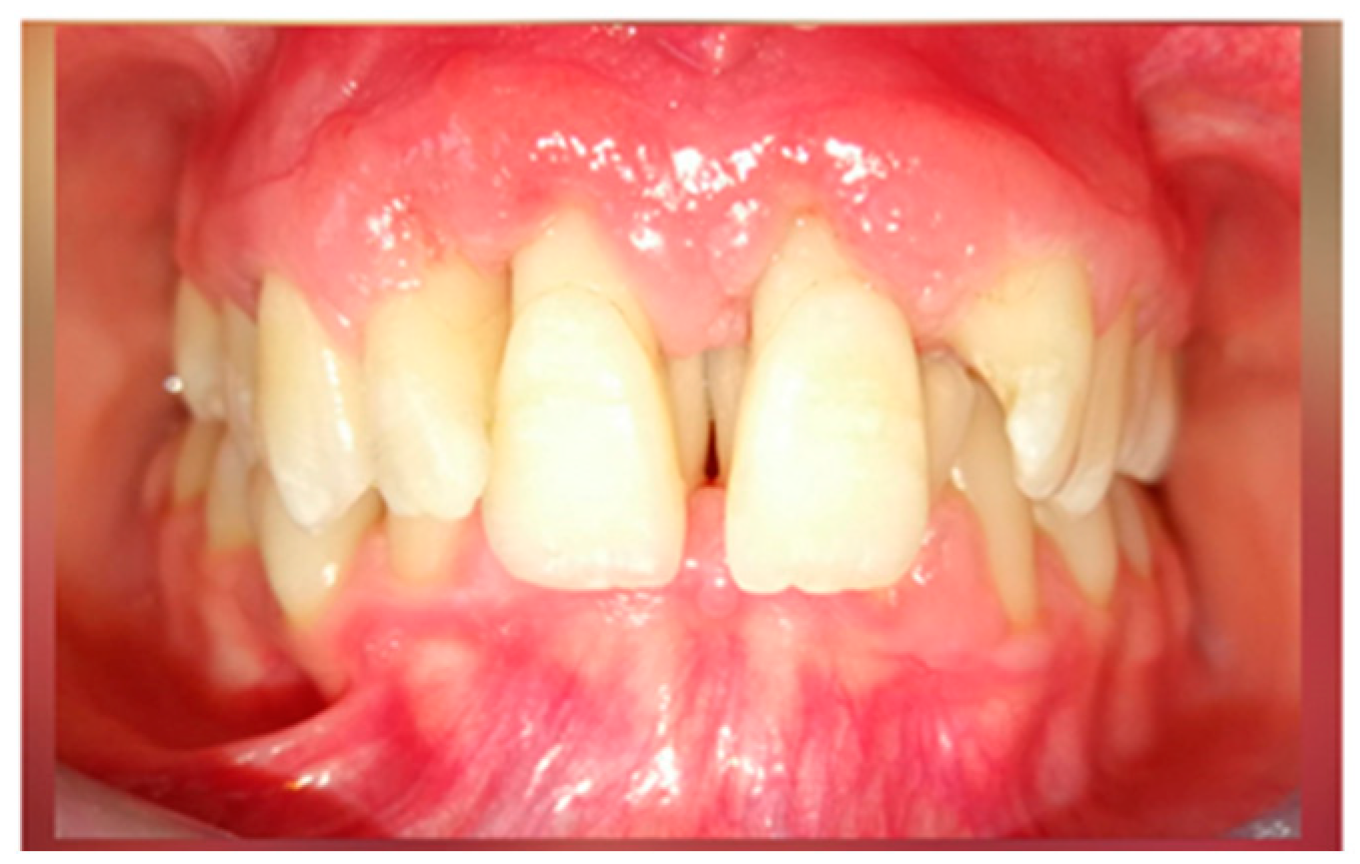

A 15-year-old female teenager was referred by a general practitioner to the Department of Periodontology, Faculty of Dental Medicine, University of Medicine and Pharmacy Carol Davila, Bucharest, Romania. There were no other diseases, such as diabetes or other hematological disease, no smoking, and no medications being taken by the patient. She had an accident (falling down the stairs) when she was 7 years old but did not experience any general or dental trauma (without notable objective or subjective clinical signs) as a result. Consequently, she did not visit a dentist for any treatment. The reasons for the first visit were teeth mobility, which appeared 2 years behind, poor aesthetic aspect of gingiva, and poor masticatory performance. The following clinical parameters were assessed at baseline: bleeding upon probing (BOP), plaque index score (O’Leary et al.) [12] and probing depth (PD). All measurements were performed by the same examiner using a periodontal probe (North Carolina 15 mm probe) on six sites for each tooth. The initial examination revealed deep probing pocket depth, severe gingival overgrowth, bleeding upon probing, and gum recession. Gingival inflammation was observed. Periodontal abscesses were registered to both maxillary central incisors (Figure 1). Suppuration and tooth mobility were registered to both maxillary central and lateral incisors. Gingival overgrowth was registered mainly on the maxillary anterior tooth side.

Figure 1.

Clinical aspects before periodontal treatment: (a) frontal aspect, (b) right lateral aspect, (c) left lateral aspect, (d) maxillary occlusal aspect, and (e) mandibular occlusal aspect.

The plaque index score registered and bleeding upon probing (BOP) were 100%. The initial probing depth (PD) was 10 mm at the left central incisors (mesial) and 8–9 mm at the other proximal sites of the both upper central incisors. The tooth mobility (Miller Classification) was Class 2 for both the maxillary central and lateral incisors (Figure 2).